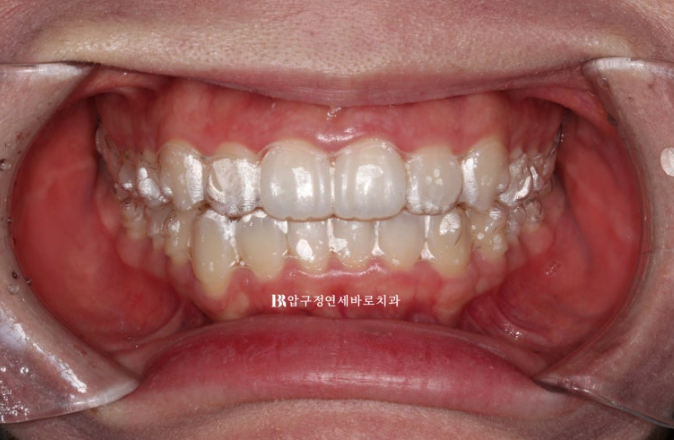

23.07

교정을 위해 내원한 환자분

윗니가 아랫니를 많이 덮어서 앞니가 깊게 물리는 과개교합이 보이고 위 아래 치아 중심선이 맞지 않습니다.